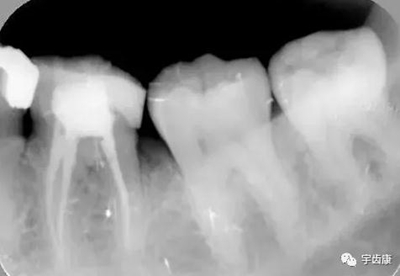

X線閱片知識(shí)

樁固位形(增加固位形和抗力形)